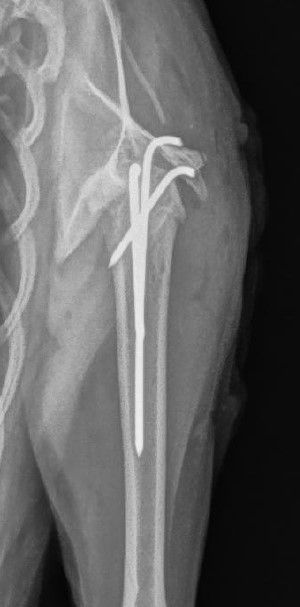

Zum Vergleich: Der gesunde rechte Oberarm

Fünf Wochen postoperativ fertigen wir erneut Röntgen an - die Fraktur verheilt schön, und Zelda läuft lahmheitsfrei. Die "Haftbedingungen" der Katze werden erleichtert (sie darf sich nun frei in der Wohnung bewegen), später darf sie dann wieder Freigang geniessen.